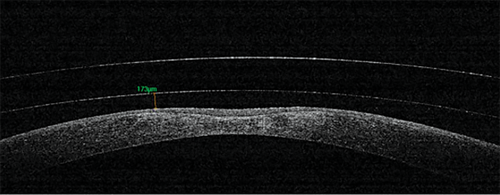

The patient’s previous best corrected visual acuity was OD 20/25 OD and 20/25 OS. With poorly fitting lenses that had been chronically applanating the patient’s cornea, the patient had resultant corneal scarring and corneal thinning that resulted in irreversible vision loss (see Figure 1).